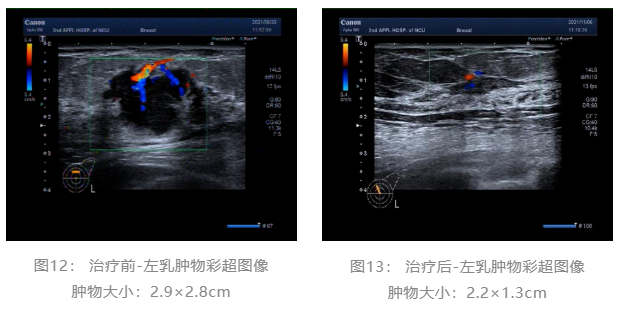

▌治疗前后影像学对比:

乳腺彩超:

术前评估:新辅助治疗期间患者无明显不适,一般状况可。新辅助治疗后左乳房肿瘤及腋下肿大淋巴结退缩明显,疗效评估PR,未发生不良事件,择期可行左乳癌改良根治术。